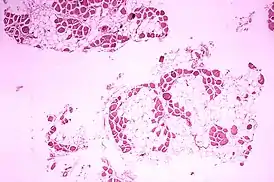

Болеют мальчики и очень редко девочки. Болезнь вызывается делециями или дупликациями одного или нескольких экзонов, либо точечными мутациями в гене дистрофина. Основное проявление — слабость мышц, затруднения при движениях с детского возраста, которые прогрессируют с течением времени. Признаками этого заболевания являются специфическая походка и осанка страдающих им мальчиков, позднее начало ходьбы, ухудшенная по сравнению со сверстниками речь, псевдогипертрофия икр[1]. Требуется лабораторная диагностика[2] — обычно речь идёт о биопсии мышечной ткани и генетическом исследовании. С 8-10 лет больным необходимы костыли, с 12 большинство из них прикованы к инвалидным коляскам, с 16-18 испытывают дыхательные нарушения. Также характерны поражения сердца (развивается кардиомиопатия[3]) и снижение интеллекта. Механизм развития последнего доподлинно не установлен. Смерть обычно наступает на втором-третьем десятилетии жизни. Средняя её продолжительность составляет 25 лет, однако есть люди, которые живут дольше[4].